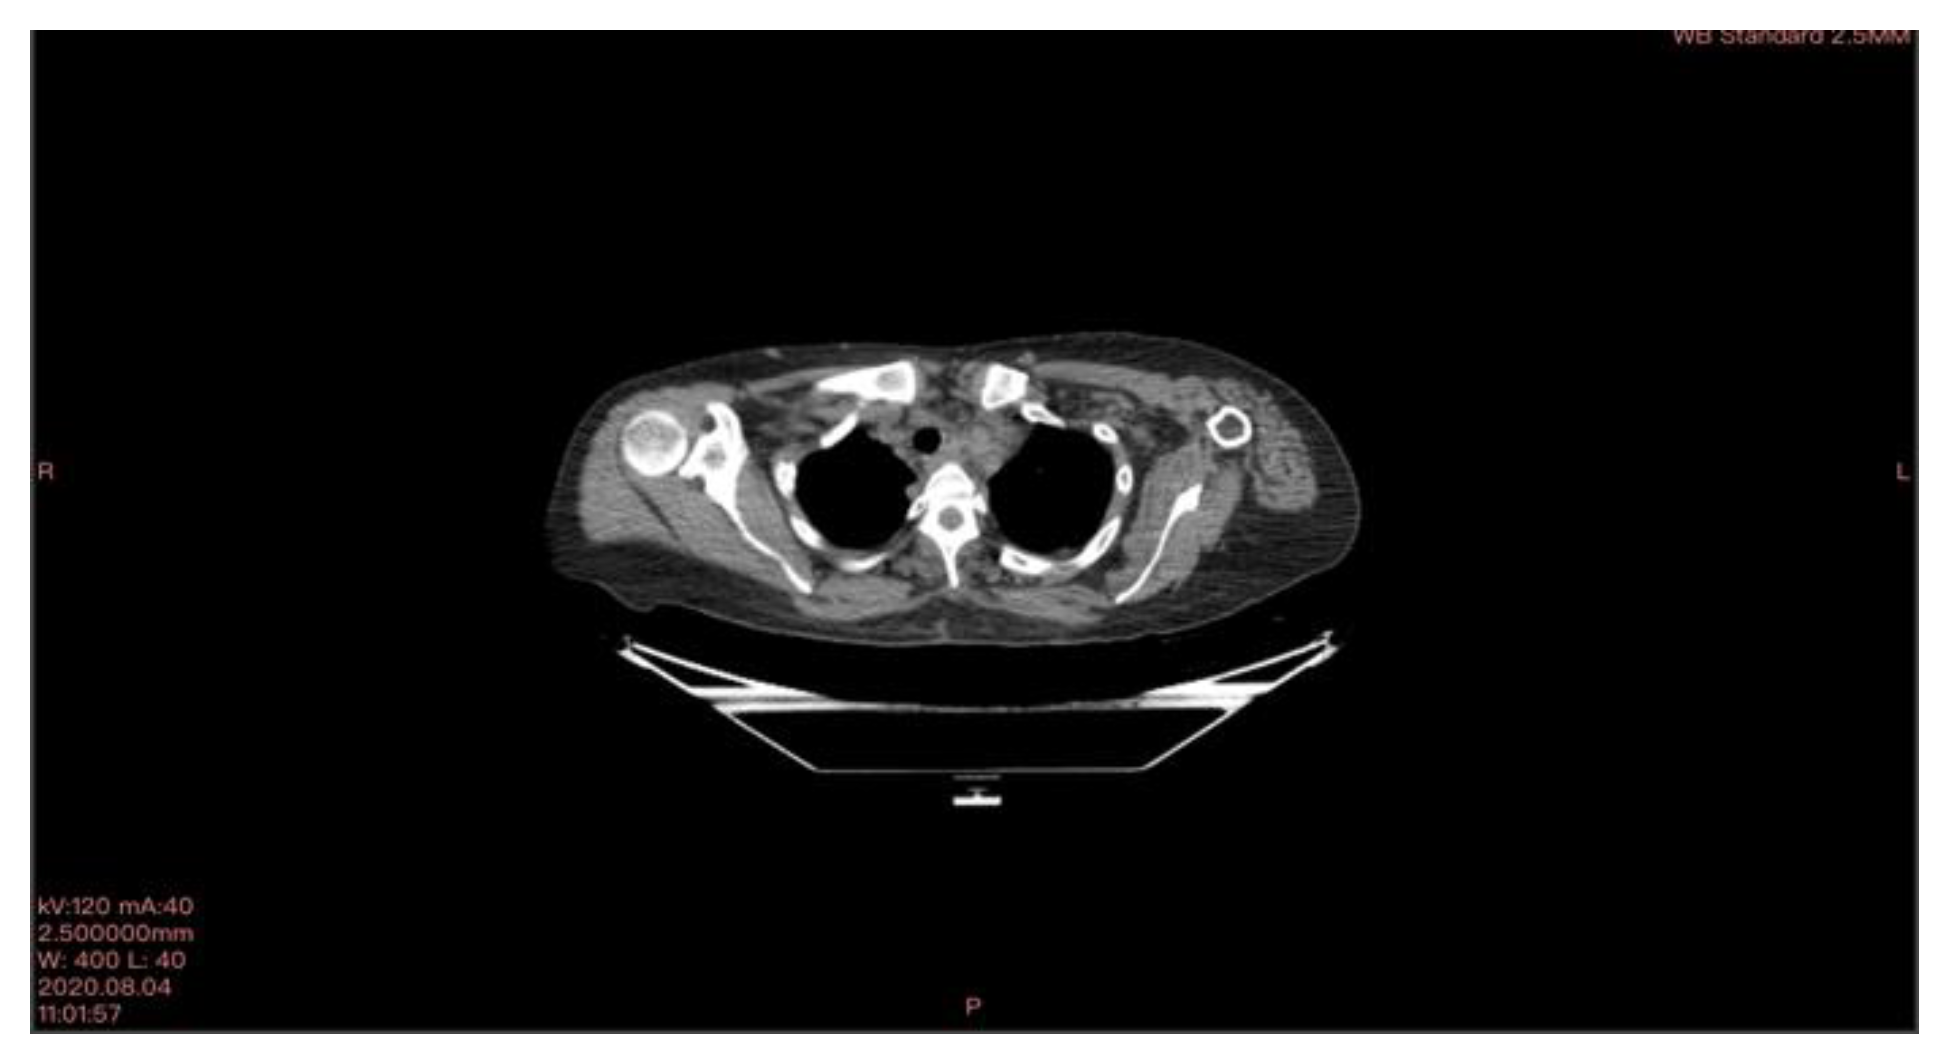

In October 2018, a 24-year-old patient arrived at our cryosurgery unit with the results of a CT scan. The presence of bilateral pulmonary and mediastinal lymph node metastases close to the esophagus was highlighted (Figure 6).

After cryotherapy and immunotherapy, very good postoperative evolution was noted, both radiological and analytical, and clinical (Figure 11).

Figure 6. CT scan images indicate the presence of bilateral pulmonary and mediastinal lymph node metastases close to the esophagus. The arrow indicates the tumor’s location.

Figure 11. CT scan images after cryotherapy in the patient with bilateral lung metastasis and mediastinal lymph nodes. The arrow indicates where the tumor was located.